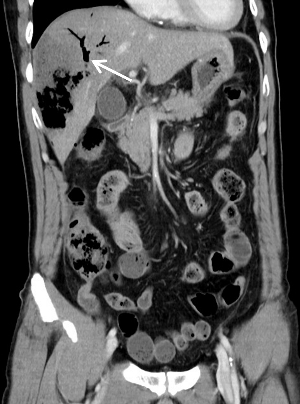

今晨零点左右上厕所后再发畏寒发热,家属发现其口唇发紫、呼吸急促,遂来本院急诊。腹部CT平扫提示肝内积气(图 2)。收住急诊抢救室,急查腹部增强CT,考虑肝脓肿致肝脏破裂(图 3)。

| 图 2 患者全腹部CT平扫示肝V段见团片状气体密度影(白色箭头所指处),腹腔可见大量游离气体(黄色箭头所指处) |

图 2患者全腹部CT平扫示肝V段见团片状气体密度影(白色箭头所指处),腹腔可见大量游离气体(黄色箭头所指处)。